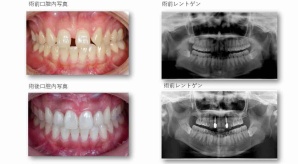

¥¤¥ó¥¹¥¿¥°¥é¥à¤ËºÜ¤»¤Æ¤¤¤ëÅö±¡¤Î¾ÉÎã¤Ç¤¹

ðÌî»õ²Ê¾ÉÎ㢠ÀèÅ··ç»¶ºÀµ¥¤¥ó¥×¥é¥ó¥È

ðÌî»õ²Ê¾ÉÎã¡¶ºÀµ¥¤¥ó¥×¥é¥ó¥È¥»¥é¥ß¥Ã¥¯